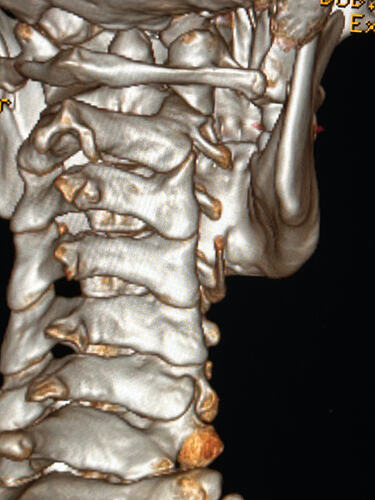

Things of note that I can see in your imaging - You’ve completely lost the natural lordotic curve in your cervical spine. That alone can bring the styloids & hyoid bone into closer proximity to nerves & vascular tissues in the neck though it has been speculated that the neck curve is lost when there’s IJV compression due to ES as the body’s way of trying to create more space for the IJV so it can drain the deoxygenated blood from the brain more efficiently. The lordotic curve can be restored w/ gentle exercises but it takes patience & is a slow process. The following link has helpful information about cervical curve restoration.

In this image of your left styloid, it appears from the angle of the picture that your left styloid is extremely close to the left transverse process of C1 (green circled area). If that’s truly the case, your left IJV is likely being squashed between the two & that means your vagus nerve is most likely being squashed at that point, too. Some of your symptoms could be vagal related. Also due to the angle of the image, it appears the greater horn of your hyoid could be very close to your spine which can cause internal/external carotid artery compression but can also cause symptoms that point to hyoid bone syndrome as you’ve suggested. Unfortunately, it doesn’t appear the CT scan was done w/ contrast as none of your veins or arteries appear in the images you posted & contrast is necessary to see those.

I’ll just add in as well that in your first image, the hyoid bone processes look pretty thick, more than you’d expect, so could well be part of your issues, but I do agree with @Isaiah_40_31 that your left styloid is very close to the C1 process, the right side looks a little longer than average… Also looking at the 1st & last images (I’m sorry, | can’t label them for you), there’s calcification below your hyoid which I’m presuming is the thyroid cartilage, it lookd pretty chunky compared to most people’s, so this could possibly be causing some issues too?

Yes these are from before my first surgery with Dr. Osborne and I had my right styloidectomy. I have also wondered about the cartilage. Last year I saw a couple of orthopedic doctors, one of whom suggested that I look into the cartilage because of how large it was and how it might be affecting my military neck and my ability to extend my neck.

I totally missed that I could see your whole hyoid bone from the front in this image. Jules is right, your greater horns are very thick from top to bottom. You can also see that your left greater horn is pretty straight, but the right one has an upward curve to it. I’m not sure what the calcification is below your hyoid but it’s most likely thyroid since the thyroid sits just below the hyoid in the neck.

In this image, you can see the differences in the shapes of your hyoid’s greater horns. The right one is more curved but the left one is thicker in width medial to lateral. In this image from the front it looks like both greater horns may be contacting your cervical spine in certain head positions, but again, that may an illusion created by the angle of the image.

In the final two images you sent, the right greater horn is very close to your cervical spine so there’s a good chance it’s causing you some problems as well as possible carotid artery irritation or compression in different head positions. The image of the left one doesn’t show as much of the greater horn so I can’t tell how close to the spine it is. Can you back the left image out a bit so it looks more like the right one?